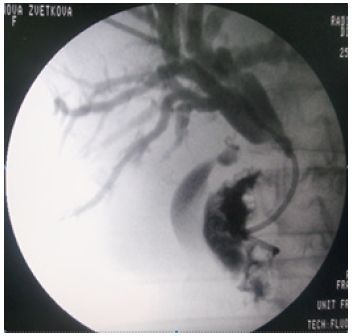

We completed that abdominal collection drainage with a percutaneous biliary drainage in the case of CBD stones and cholangitis associated with necrotic pancreatitis (Figure 9).

The indication for Percutaneous Biliary Drainage (PBD) is the same as an ERCP, which is the gold standard for the treatment of CBD stones. We apply the PBD in the setting of cholangitis, biliary obstruction and suspected choledocholithiasis [23]. The delay between the patients’ admission and intervention usually takes 2 weeks in our study. For eleven patients the laparoscopic necrosectomy was used in the second week after the onset of AP due to deterioration of patients’ general condition and the risk of septic shock. According to a recent study the walled-off necrosis may develop sooner than 4 weeks of the onset of AP. In this study 43% of well-defined collections were shown on imaging within 3 weeks of onset [24].